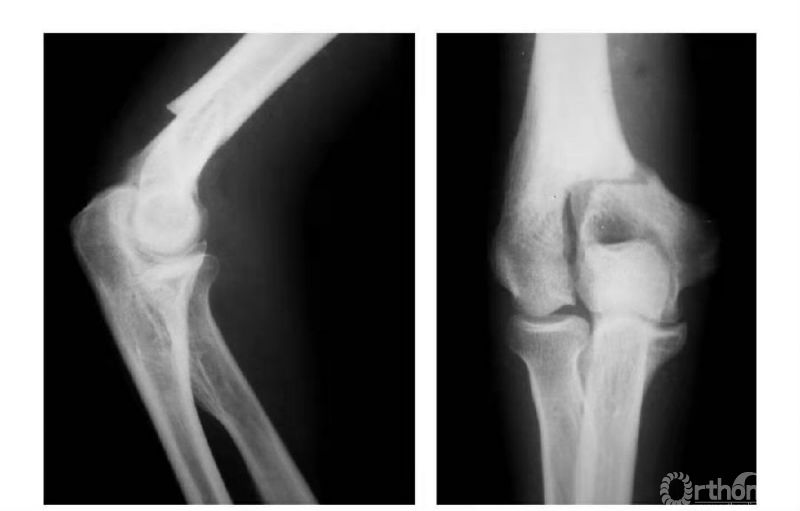

例1:肱骨内髁骨折,折线由滑车外缘沿鹰嘴窝上缘,并呈直角状而拐向内上髁(属于稳定型)(图1)。

图1

例2:肱骨内髁骨折,折线经滑车外缘斜向内髁上部(非稳定型)(图2)。

图2